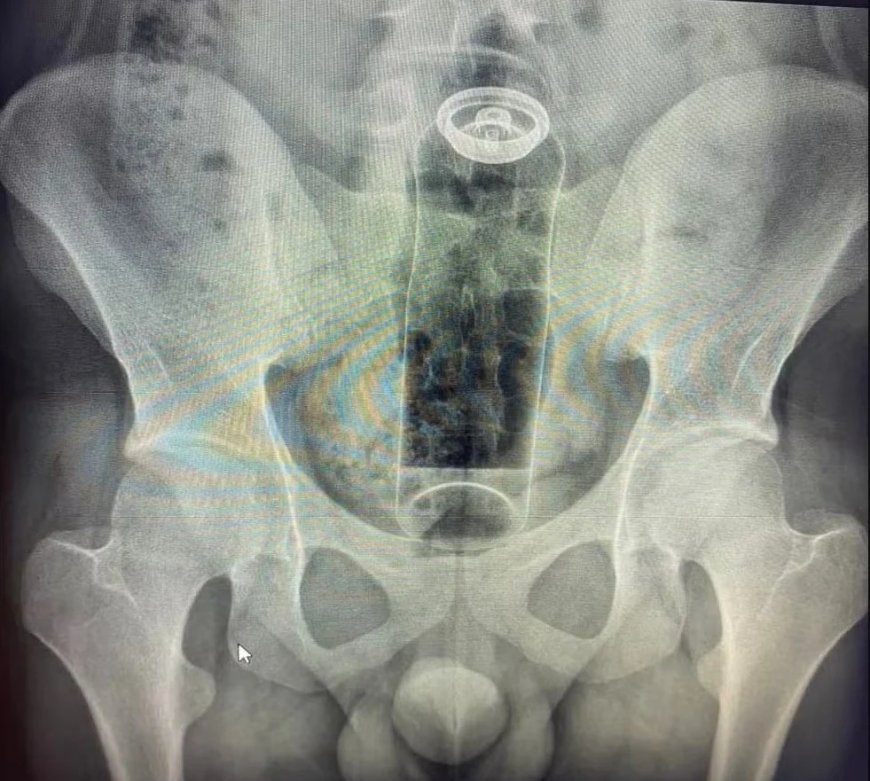

Seja por curiosidade, para apimentar a relação ou para experimentar a própria sexualidade, há quem goste de explorar o prazer na região anal na “hora h”. Especialistas explicam, no entanto, que é preciso cuidado com o que é introduzido. Um médico usou as redes sociais para fazer o alerta depois de atender um jovem que precisou ser internado para retirar um desodorante do reto. (Veja a imagem acima)

De acordo com o médico Daniel Brosco, cirurgião coloproctologista, o paciente tinha 19 anos e contou que colocou o desodorante no ânus durante uma “brincadeira” sexual. A embalagem, porém, acabou subindo para o reto e não conseguiu ser retirada em casa. (Veja a imagem abaixo)